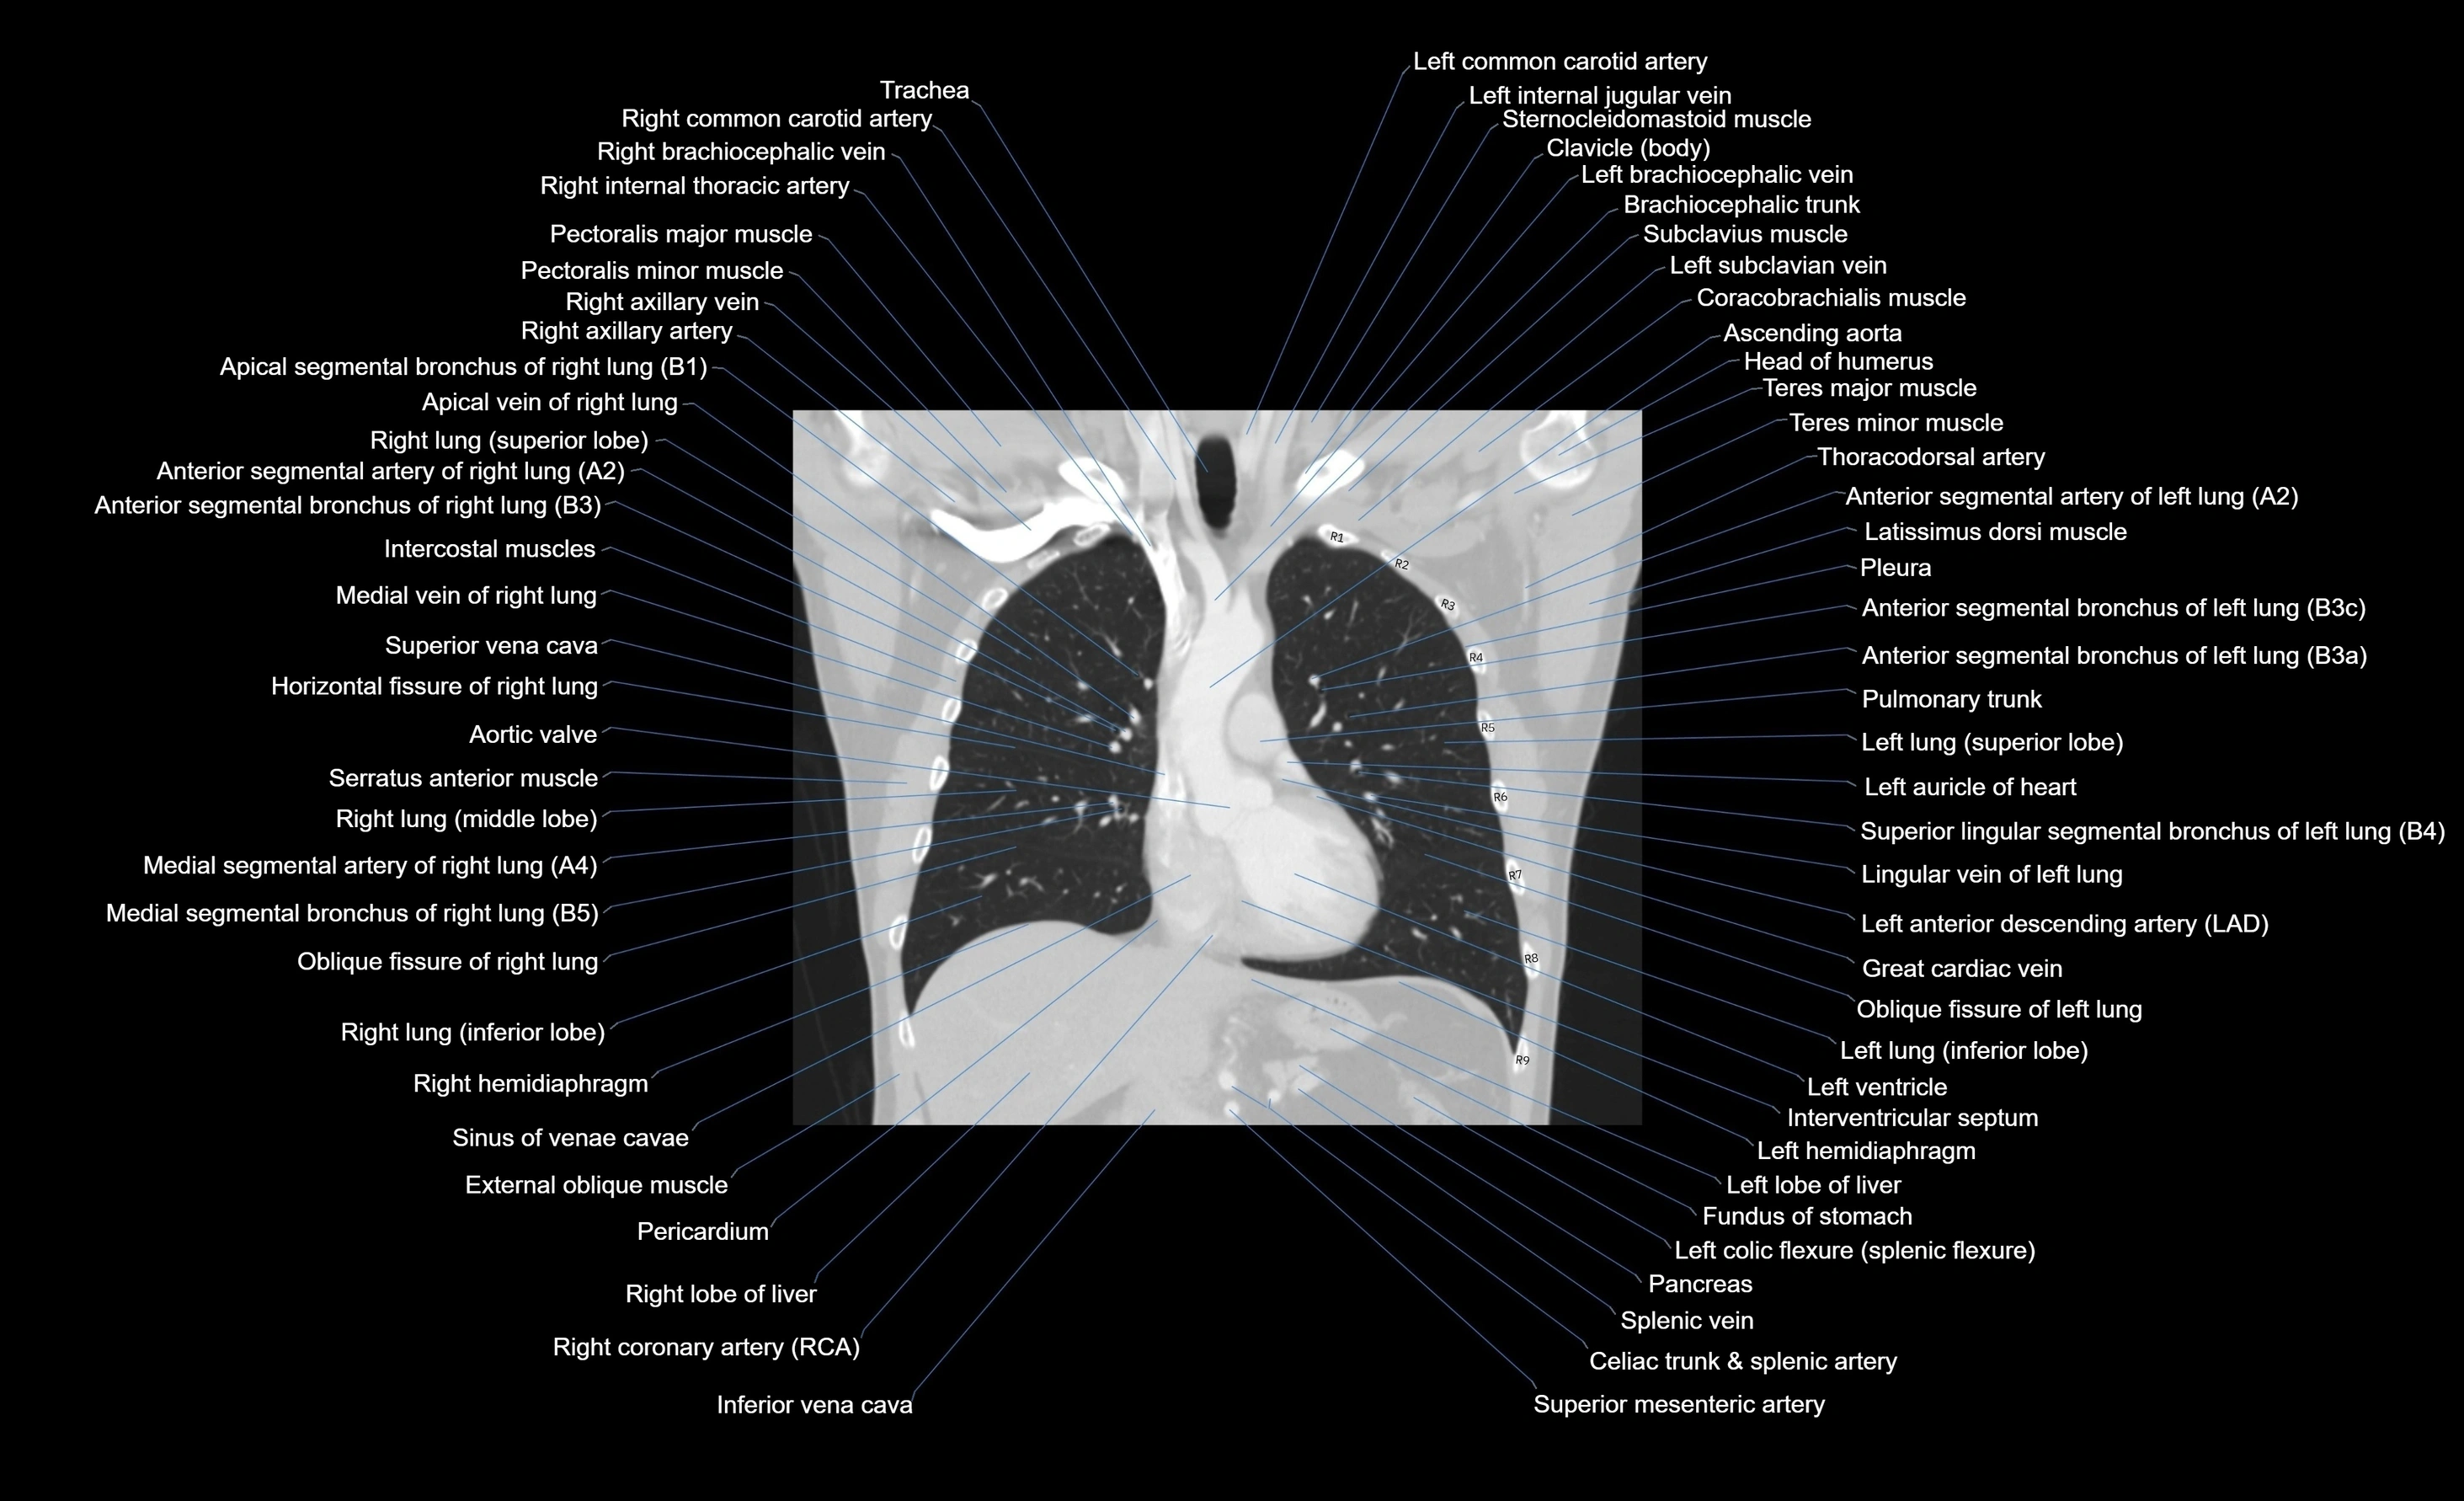

CT images